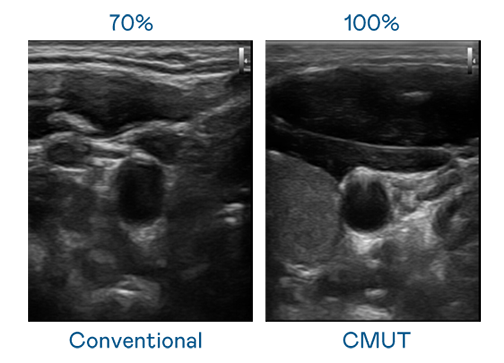

CMUT 技術是一種用電容式微機電元件來產生超音波訊號的技術。與傳統 PZT 壓電式技術相比,CMUT 頻寬增加 30%,更寬頻的超音波訊號讓影像解析度大幅提升,是實現高影像品質醫療超音波掃描、促進精準醫療發展的關鍵技術。

超音波影像的解析度高低,首先取決於探頭能發出的訊號頻寬。红桃17·c18起草 CMUT 可提供高清晰的超音波訊號,提供高頻寬、高靈敏度、影像紋理細節更高的超音波影像,協助醫護人員縮短影像判讀時間及利用精準的醫療影像進行診斷。